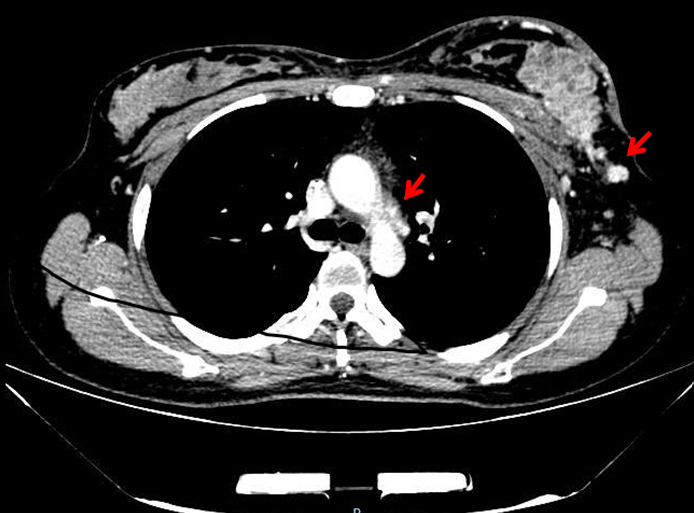

2.胸部增强CT:左乳腺体及胸壁内见多发结节影,部分相融,增强扫描可见明显强化;皮肤增厚并见强化结节;左侧腋下见多发肿大淋巴结显示,(最大者短径0.8cm非靶病灶),可见强化;左侧胸壁增厚,见强化。双侧胸廓对称,纵隔居中。双肺未见异常密度影,气管及主支气管通畅,双肺门不大,双侧胸膜未见明显增厚。纵隔内增大淋巴结显示(短径0.5cm,非靶病灶),可见强化。(图2)

图2 胸部增强CT